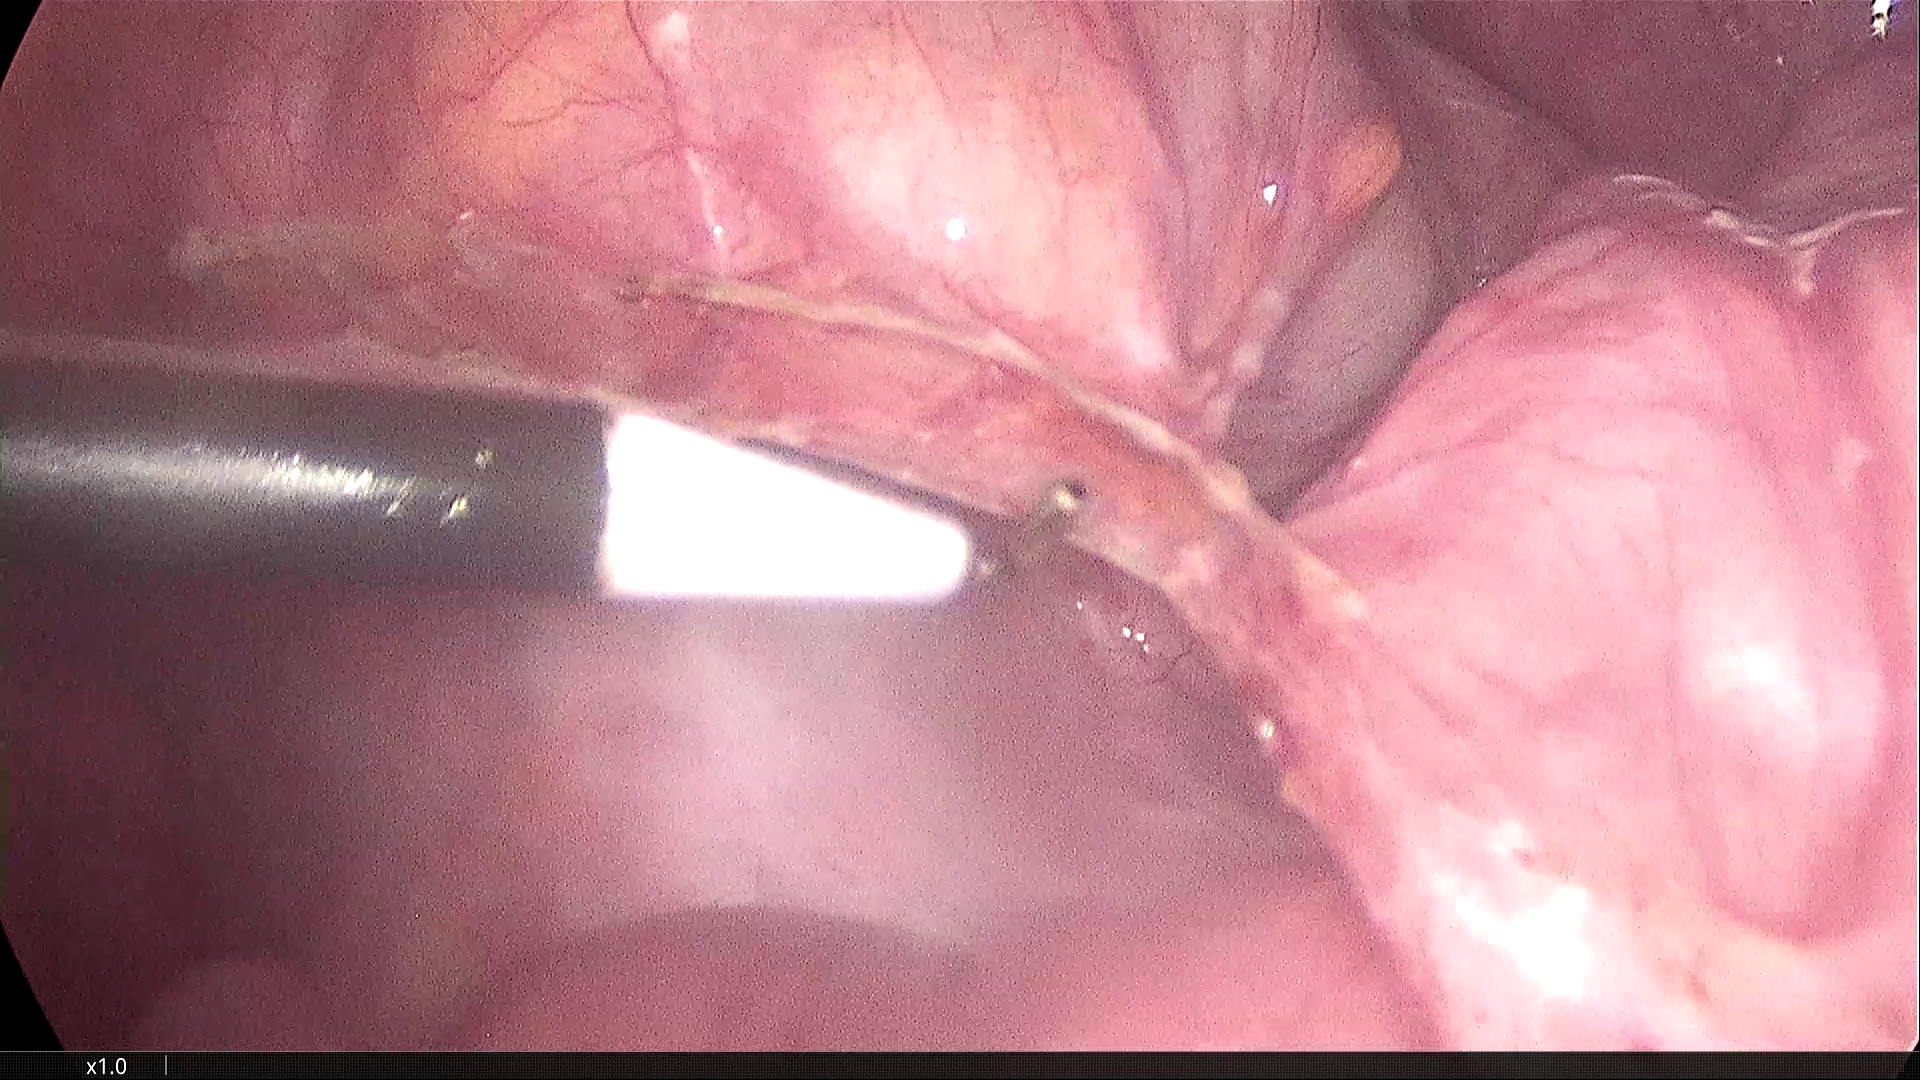

2021-3-31腹腔镜探查,脐部闭合穿刺置入腹腔镜,为观察孔。左下腹及下腹正中分别作操作孔,腹腔镜探查,腹膜光滑,腹腔无积液,胃肠道柔软,空回肠结肠无扩张。无游离大网膜,右下腹无游离肠襻,区域性的回肠肠襻为软膜样组织覆盖包裹,无明显炎症反应。包裹团块张力不高,内侧与乙状结肠系膜呈纤维组织粘连。锐性分离,无明显渗出。自后腹壁锐性切开包膜,显露其内迂曲回肠襻,形态大致正常,与包膜呈一般纤维组织性间隙,易于分离。包膜内肠管间有数条致密粘连纤维索带,予以切除。切除大部包膜组织,完全解放其中的回肠及阑尾远端部分。局部创面少许渗出,自回盲部顺序近端探查检视所有系膜小肠,见肠管及系膜自然正常形态,肠道畅通,未见憩室、肿物及外压扭转等病变。包膜包裹段回肠120cm,肠壁、系膜柔顺无损伤。直肠及盆腔未见明显异常,置腹腔引流管一根。

乙状结肠与回肠襻包裹膜的纤维粘连

包裹回肠襻的纤维膜